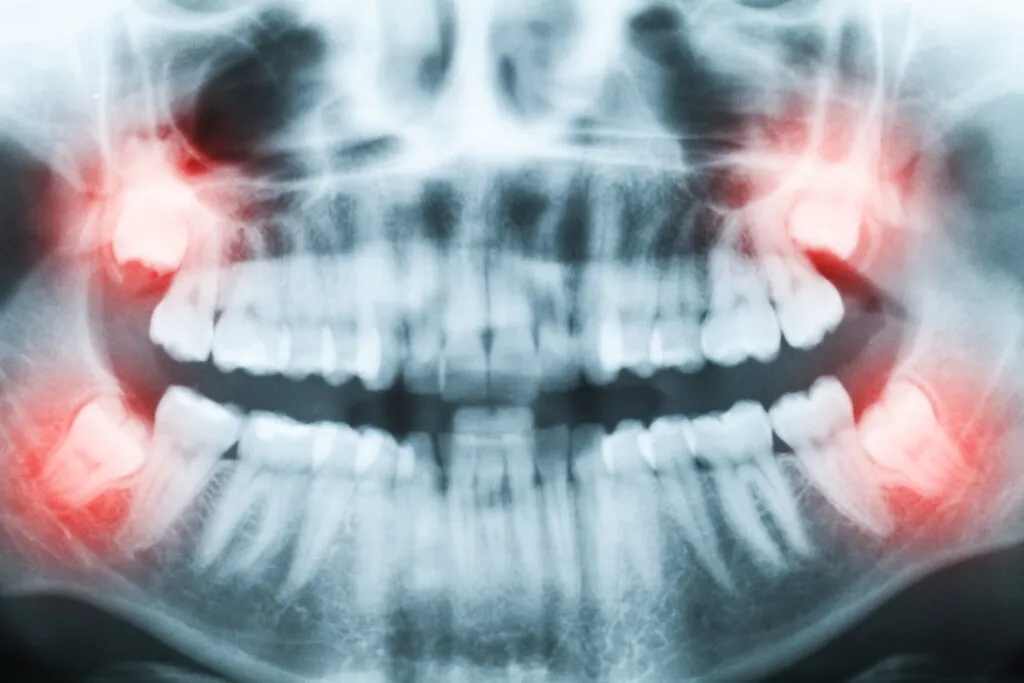

Zęby zatrzymane, czyli cichy problem z ósemkami: Szczególnie zęby mądrości, czyli ósemki, często mają problem z prawidłowym wyrżnięciem się. Mogą pozostawać całkowicie zatrzymane w kości lub wyrzynać się tylko częściowo. Taki stan może prowadzić do silnego bólu, nawracających stanów zapalnych dziąseł, a także powodować ucisk na sąsiednie zęby, prowadząc do ich uszkodzenia lub stłoczenia.

Konsultacja i diagnostyka od zdjęcia RTG do planu działania: Zanim dojdzie do ekstrakcji, niezbędna jest konsultacja z lekarzem. Stomatolog oceni stan zęba, zazwyczaj wykonując zdjęcie rentgenowskie (RTG). Zdjęcie to pozwala dokładnie obejrzeć korzenie zęba, ich kształt, liczbę oraz ewentualne zmiany patologiczne w kości. Na podstawie tych informacji lekarz opracowuje indywidualny plan zabiegu, informując pacjenta o jego przebiegu.

Ekstrakcja chirurgiczna: Jest konieczna w trudniejszych przypadkach, na przykład gdy ząb jest zatrzymany, ma nietypową budowę korzeni, jest złamany lub znajduje się w trudno dostępnym miejscu. Zabieg ten wymaga nacięcia dziąsła, a często także niewielkiego usunięcia fragmentu kości otaczającej ząb, aby go uwolnić. Po usunięciu zęba, rana jest zazwyczaj zaopatrywana szwami.

Chirurgiczne usunięcie ósemki dlaczego jest droższe? Chirurgiczne usunięcie zęba, a w szczególności zatrzymanej ósemki, jest zabiegiem znacznie bardziej skomplikowanym i czasochłonnym, stąd też jego cena jest wyższa. Koszt takiego zabiegu może wynosić od 500 zł do nawet 1500 zł. Wynika to z konieczności wykonania nacięcia dziąsła, ewentualnego rozwiercenia kości, a także późniejszego szycia rany. Dłuższy czas trwania procedury i użycie specjalistycznego sprzętu również wpływają na wyższą cenę.